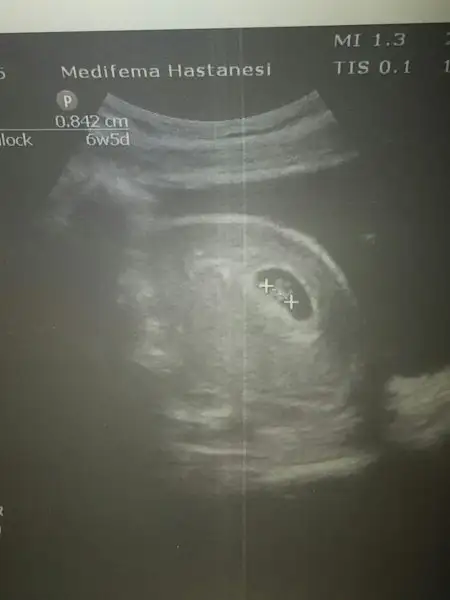

bebegin7-8 haftalıkkenki usg resimine direkt baktıgınızda;

bebek kesenin soluna yakınsa bebek erkek,

sagına yakınsa kız.

Senin bebek sola yakin,vajinal usg ile karından usg farklı.o yüzden seninki karındanmis bu teoriye erkek oluyor cnm.